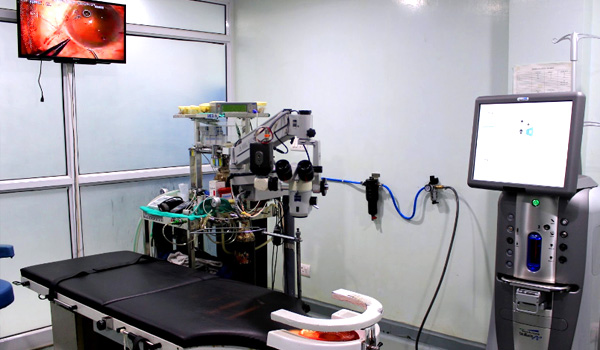

Neera Eye Center is a comprehensive eye care hospital located in Delhi. It is one of the leading eye centers in the country, offering state-of-the-art modern diagnostic, therapeutic, and rehabilitative services of the highest quality in ophthalmology. Registered with Directorate of Health Services, Government of the National Capital Territory of Delhi, doctors at Neera Eye Center are committed in providing better vision by interfacing cutting edge technology with a human touch.